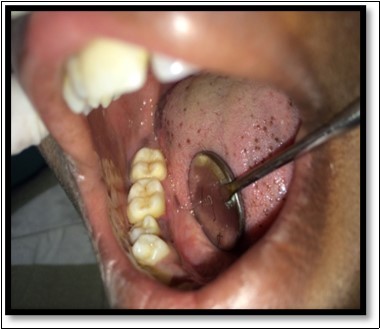

During the next visit local anesthesia was given. The lesion was excised with the help of soft tissue laser and sent for histological examination. (Figure 2) Histological report confirmed the lesion is Peripheral cemento-ossifying Fibroma. Histological analysis showed lesional tissue comprising of both trabecular bone and woven bone. Periphery of the lesion showed numerous globular and irregular cementum like calcification. In most areas these calcification coalesced with each other forming bigger calcification. The supporting connective tissue stroma was loose fibrillar with less cellularity. Detached overlying parakeratinized epithelium was observed in one area. (Figure 3) Post operative evaluation revealed normal healing after one month. (Figure 4)